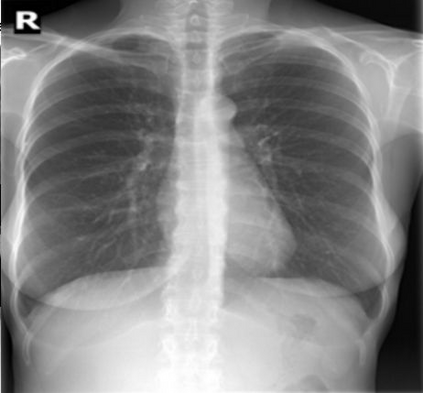

The evaluation of infectious disease processes on radiologic images is an important and challenging task in medical image analysis. Pulmonary infections can often be best imaged and evaluated through computed tomography (CT) scans, which are often not available in low-resource environments and difficult to obtain for critically ill patients. On the other hand, X-ray, a different type of imaging procedure, is inexpensive, often available at the bedside and more widely available, but offers a simpler, two dimensional image. We show that by relying on a model that learns to generate CT images from X-rays synthetically, we can improve the automatic disease classification accuracy and provide clinicians with a different look at the pulmonary disease process. Specifically, we investigate Tuberculosis (TB), a deadly bacterial infectious disease that predominantly affects the lungs, but also other organ systems. We show that relying on synthetically generated CT improves TB identification by 7.50% and distinguishes TB properties up to 12.16% better than the X-ray baseline.